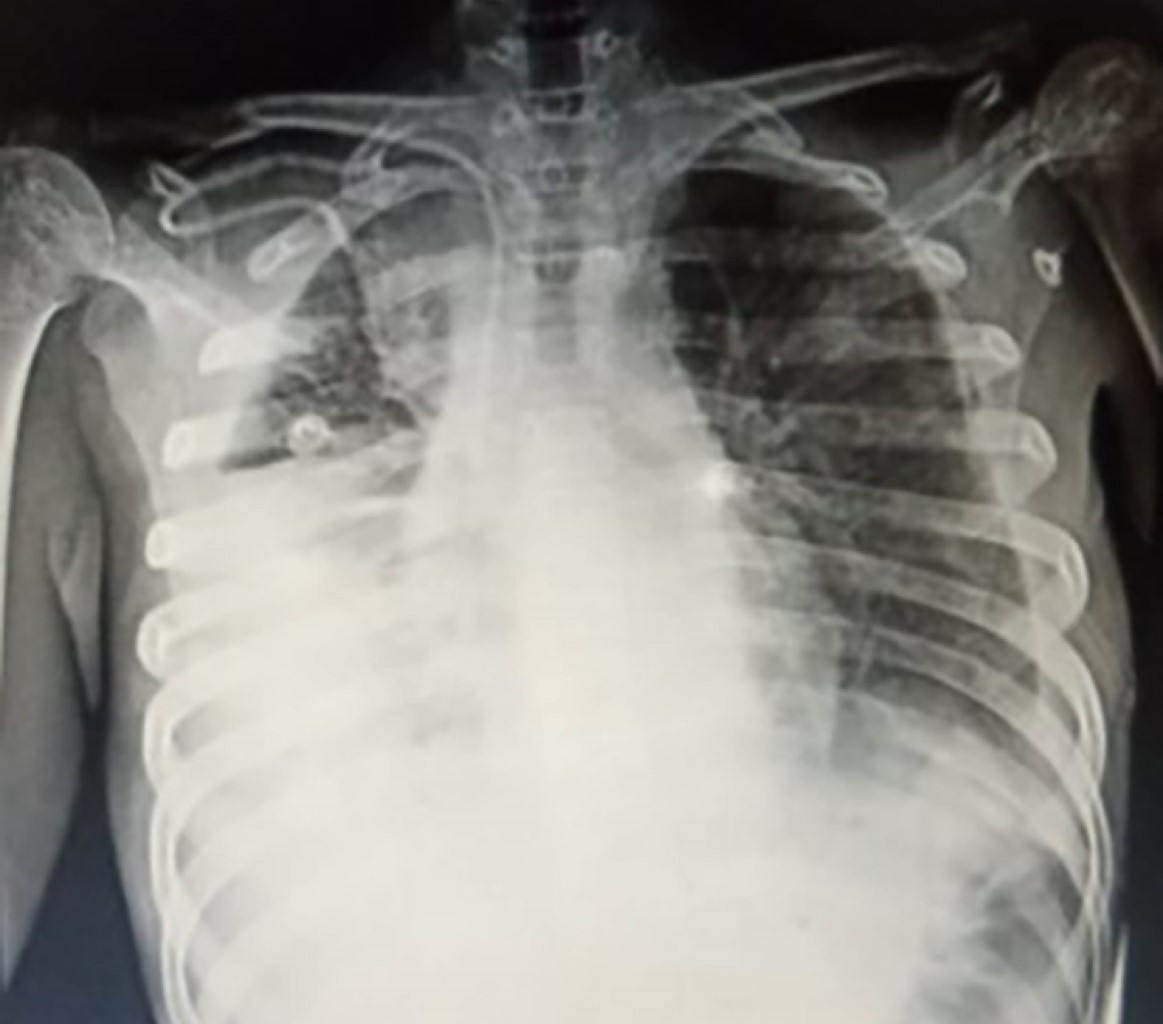

Estado al ingreso: presenta dificultad respiratoria de inicio insidioso y leve, a nivel torácico se ausculta hipoventilación y matidez basal de predominio derecho, a nivel abdominal hepatomegalia y esplenomegalia. Espalda baja con aumento de volumen, cadera izquierda con aumento de temperatura local, con dificultad para la bipedestación y la marcha, con ayuda de ortesis para su traslado. Por último, a nivel de genitales se halla hidrocele izquierda. Motivo por el cual se inicia protocolo de estudio con toma de radiográfico de tórax, el cual mostró derrame pleural en hemitórax derecho de etiología a determinar (Figura 1). Ameritó manejo por el servicio de cirugía para colocación de sello pleural con drenaje de alto gasto 3,400 mL de características lechoso, turbio, quilo con aumento del gasto de 4,500 cm3 con un total de 7,900 cm3. Durante su estancia hospitalaria se realiza reposición de líquidos a 100% más albumina. Así como manejo con oxígeno suplementario 5 L/min y antibioticoterapia con doble esquema de ceftriaxona y clindamicina. Se recaba estudio citológico y citoquímico de líquido pleural en el cual se halló un aumento de triglicéridos, por lo que se inicia manejo con octreotide. Tras una evolución tórpida, donde aumenta el gasto del quilotórax, con aumento de requerimiento de oxígeno a 7 L/min, una atelectasia sobreagregada y datos ultrasonográficos de fungomas en bazo, se inician cuidados avanzados por el servicio de unidad de cuidado intensivos (UCI) y se agrega anfotericina B al esquema antimicrobiano. Por otro lado, se realiza protocolo de estudio de baciloscopias seriadas para descartar tuberculosis ósea y marcadores tumorales con reporte negativos para ambos (fracción beta gonadotropina coriónica humana (GCH) 0.100 y alfafetoproteína (AFP) 0.60).

Figura 1